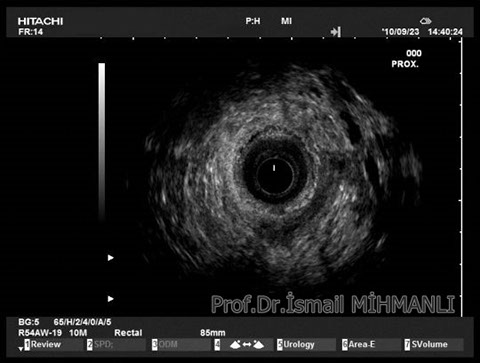

Crohn hastasında parİanal enflamatuvar hastalık